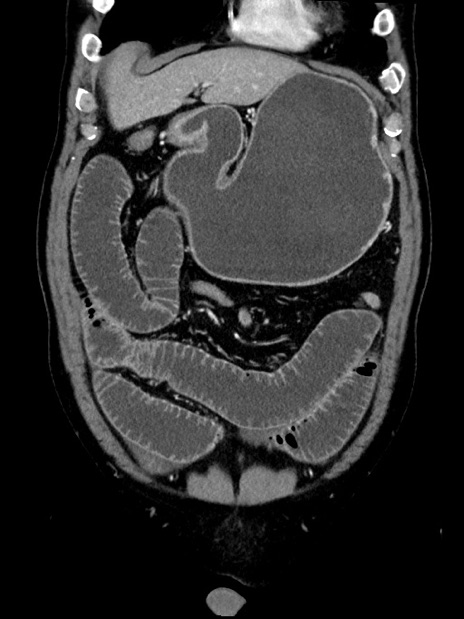

症例35(冠状断像)

【症例】70歳代 男性

【主訴】腹部膨満、嘔吐

【現病歴】昨日より腹部膨満感出現。本日増悪し、仙痛出現。嘔吐あり、受診。

【既往歴】糖尿病、胆摘後

【身体所見】BP 149/80mmHg、HR 74/min、BT 35.9℃、腹部:膨満、軟、圧痛なし。腸雑音減弱あり。上腹部正中切開瘢痕あり。

【データ】WBC 13500、CRP 1.72